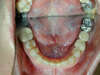

L'appareillage utilisé